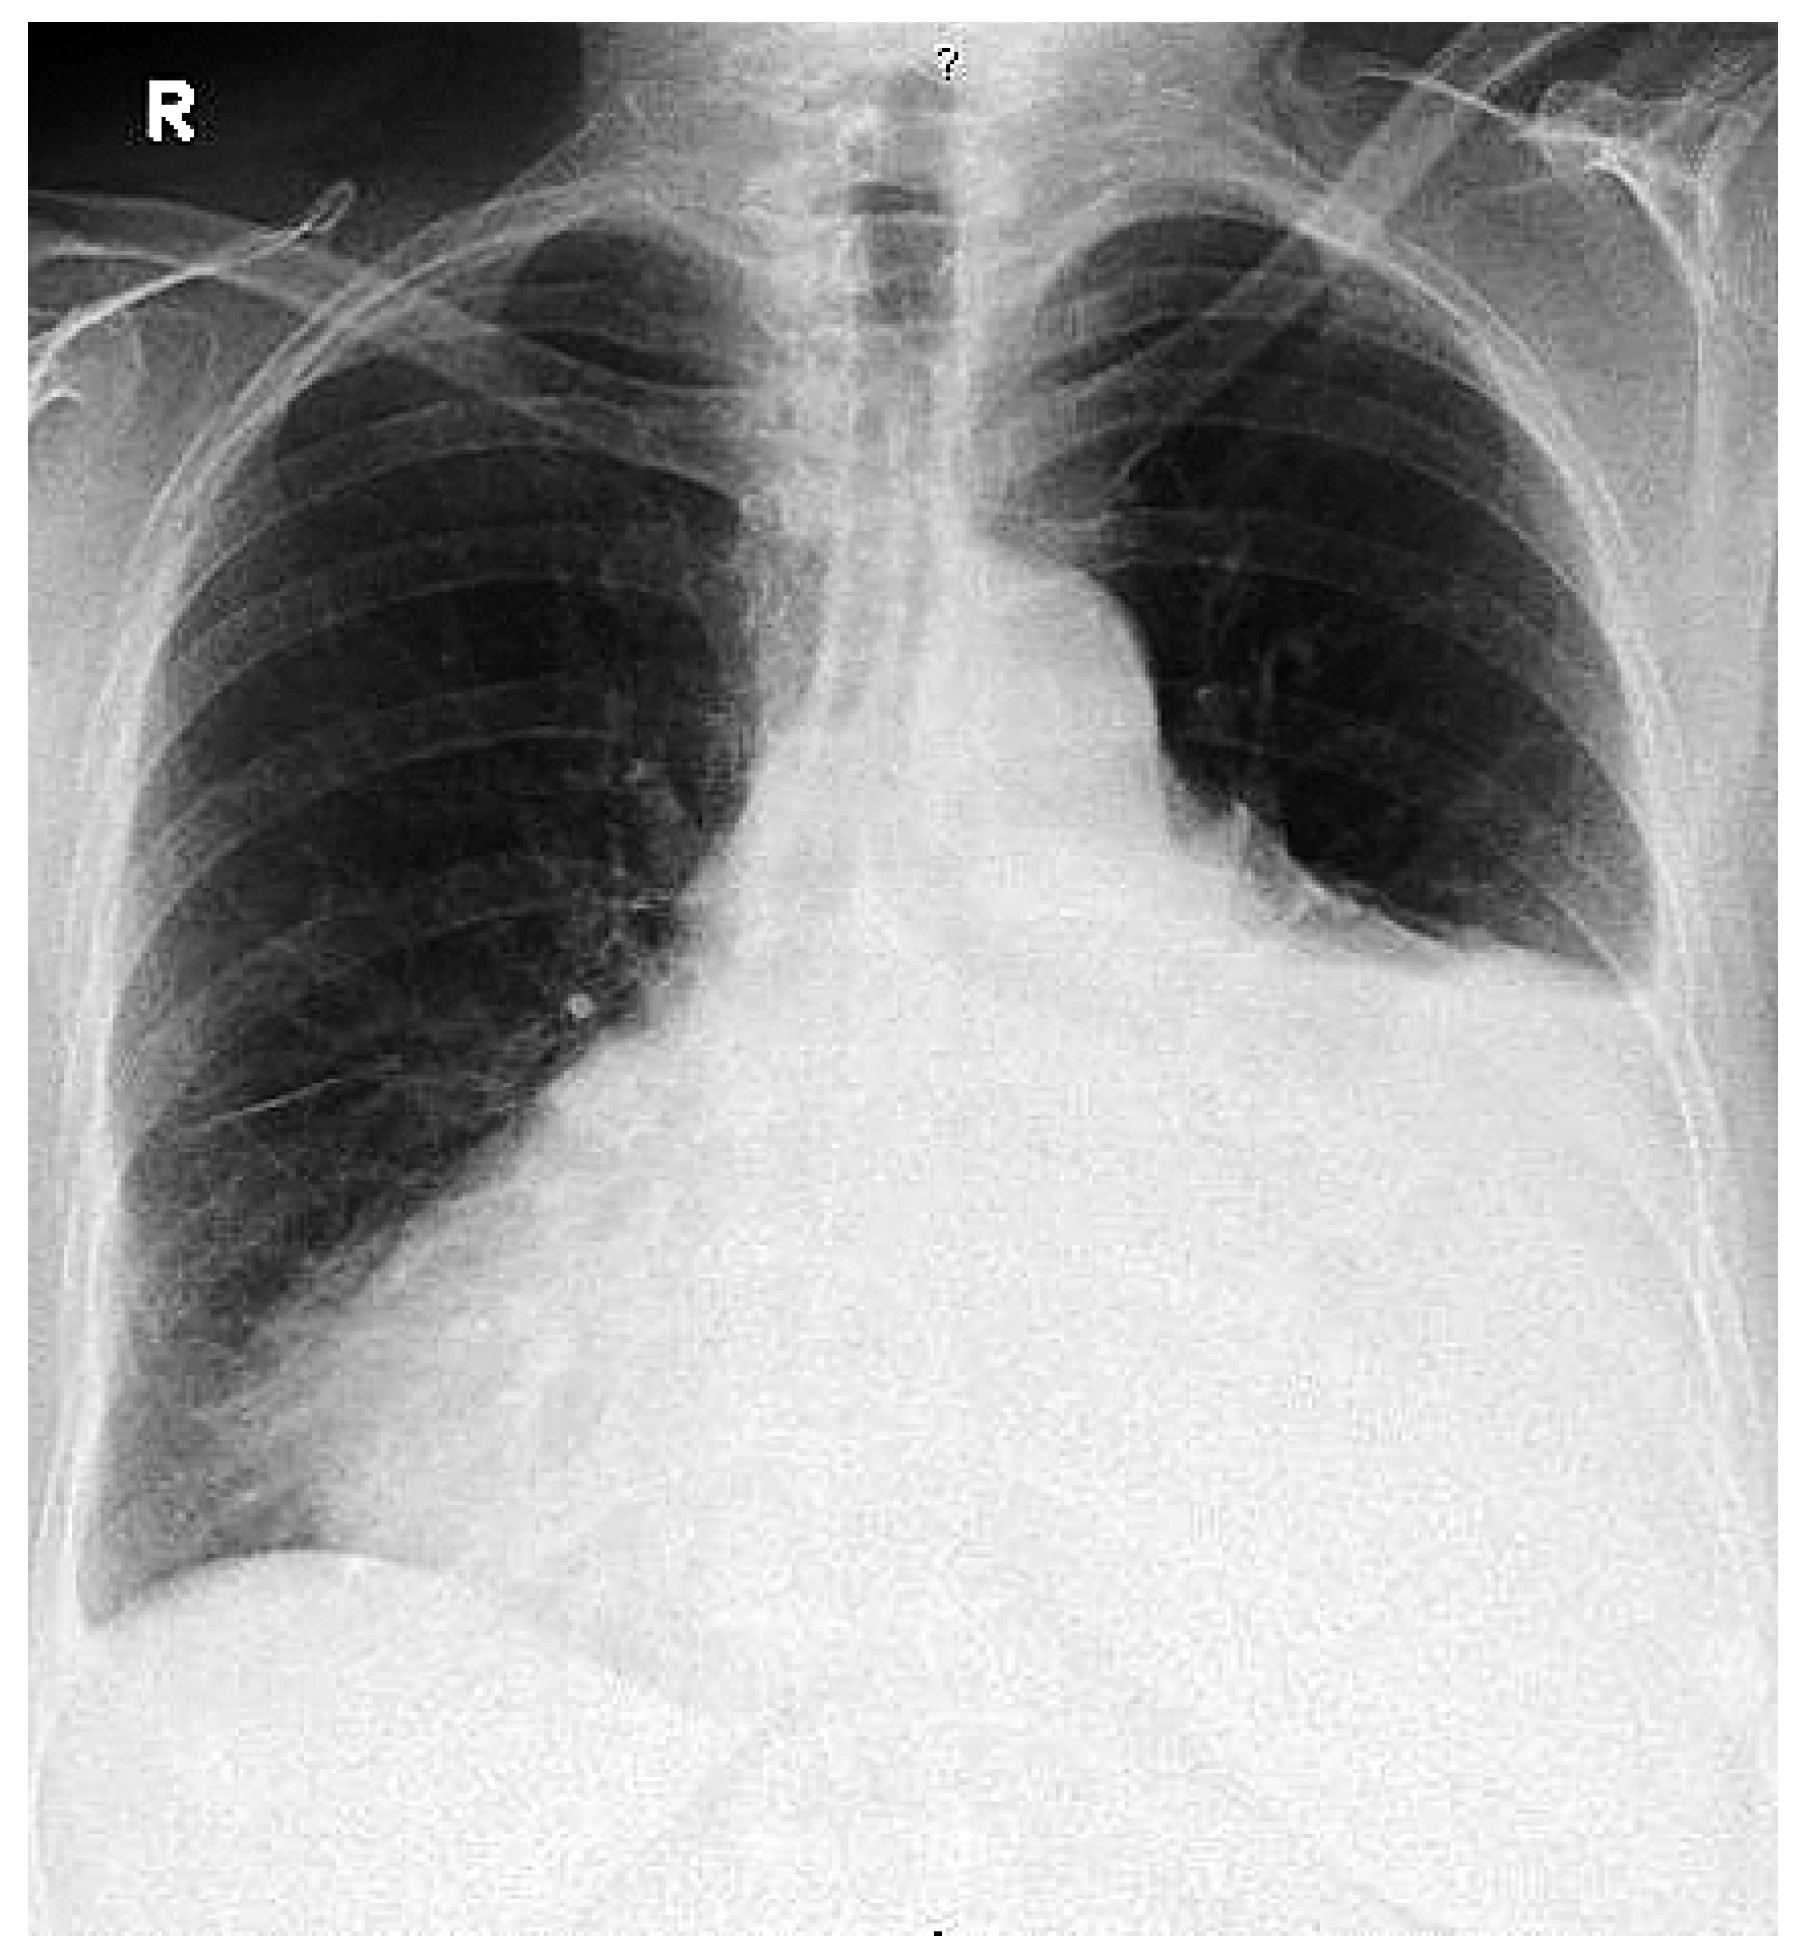

On admission she was dyspneic and orthopneic. Physical examination revealed mild malleolar oedema, a pericardial rub, fine basal pulmonary rales, normal heart sounds and no jugular venous distention. Blood pressure was 180/105 mm Hg, heart rate 80/min and temperature 36.3 °C. White blood cell count was 7.8 × 106/ml3 (36% band forms, 48% segmented forms, 11% lymphocyte, 4% monocyte, 1% basophile), thrombocyte count 579 × 106/ml3, haemoglobin 12.1 g/dl (erythrocyte indices within normal range). Significant biochemical results were: C-reactive protein 145 mg/l, alkaline phosphatase 148 U/l, creatine kinase 279 U/l, troponin T 0.11 ng/ml and Brain-Natriuretic-Peptide 196 pg/ml. Thyrotropin level was 12.41 mU/l (reference 0.25–5.0 mU/l), T3 level <0.4 pmol/l (reference 4.0–8.3 pmol/l) and T4 level <0.3 pmol/l (7.5–21.1 pmol/l). Antinuclear antibodies were 1:160 (reference <1:10). Normal serum values were found for creatinine, glucose (5.8 mmol/l), sodium potassium, ASAT, LDH (329 mmol/l) and total cholesterol. Rheumatoid factors, anti-neutrophil cytoplasmic antibodies, C3/C4 complement factors and CD4-/CD8-lymphocyte counts were within normal ranges. Electrocardiogram showed a regular sinus rhythm, small septal R and unspecific T-changes. A chest x-ray revealed a large cardiac silhouette, large left hemi thoracic effusion and blunting of the right costophrenical angle (fig. 1). CT scan of the chest showed massive pericardial effusion and some pleural effusion (fig. 2) bilaterally. Cardiac tamponade was ruled out by echocardiogram. 600 ml of straw coloured pericardial fluid was percutaneously drained. The fluid contained 8.0 × 106 leucocytes/ml3 (34% neutrophils, 56.5% lymphocytes). Glucose level was 2.7 mmol/l, LDH 3380 U/l, and total protein was 50.3 g/l. Repeated blood cultures remained sterile. However, cultures of pericardial effusion grew Salmonella enteritidis. Oral thyroxine substitution and antibiotic therapy with ciprofloxacin was started, the latter was maintained for a total of two weeks with progressive clinical and radiologic improvement. On follow-up six weeks after admission, the patient was in good condition and an echocardiogram showed only minimal pericardial effusion.

Figure 1.

Enlarged cardiac silhouette, pleural effusion on the left side.

Figure 1.

Enlarged cardiac silhouette, pleural effusion on the left side.